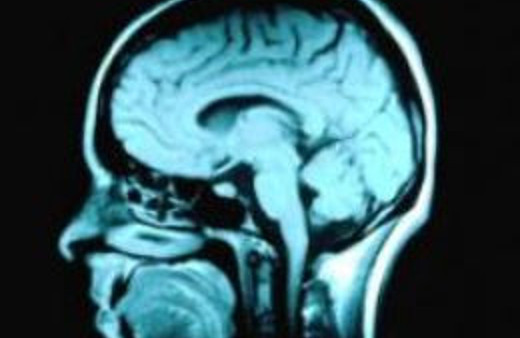

Akıl Sağlığı